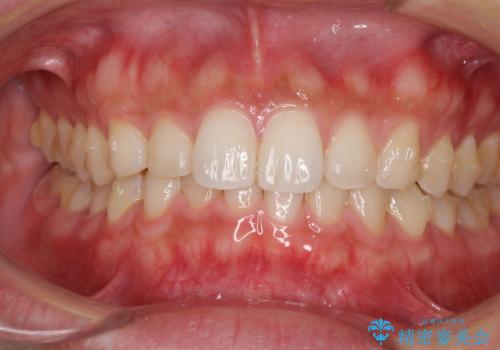

細かい隙間にものがはさまる インビザラインによる矯正治療

- 上下の前歯の隙間を気にして来院された患者様です。

インビザラインを用い、上下歯列のスペースを閉じていくこととしました。